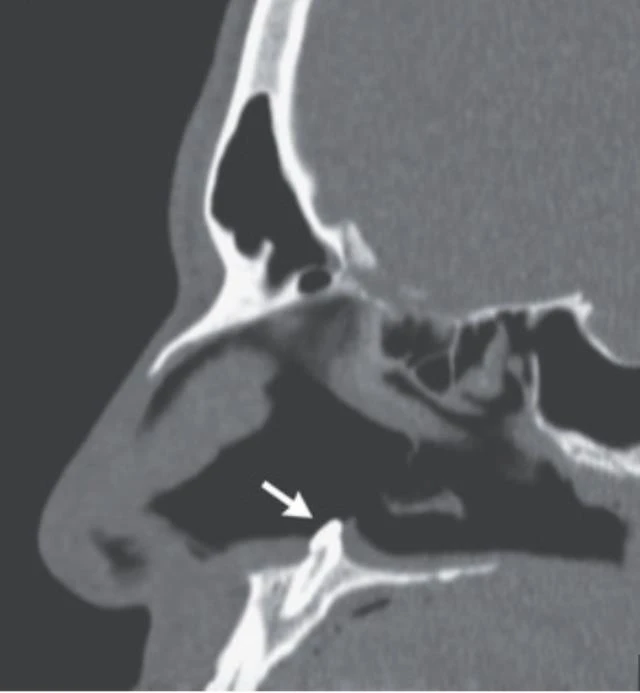

İşte hastanın burnunda bulunan diş

38 yaşındaki adamın burnundaki diş ameliyatta başarıyla çıkarıldı. Tıp dünyasında eşi benzeri görülmeyen olay New England Tıp Dergisi'nde de yayınlandı. Dergideki yazıda, şu ifadelere yer verildi:

"Hasta birkaç yıldan bu yana burun tıkanıklığı yaşadığını belirtti ancak daha önce yüz travması ya da başka bir anormallikle karşılaşmadığını anlattı. İlk muayenenin ardından buruna takılan kamera sayesinde, burunda olmaması gereken bir diş parçası tespit edildi. Bu parça başarılı ameliyat sonucu alındı.''